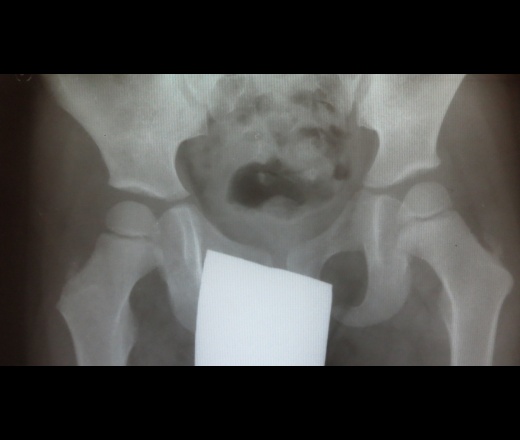

Ребенок 4 годков очень живенький и шкодненький малыш ......Жалоб конечно у него нет а вот у мамочки "куча" жалоб....Обратились в местную амбулаторию к хирургу а он в свою очередь к нам с диагнозом "боезнь Пертеса"Что скажите коллеги

Пертес обошел малыша стороной.

и я о том же